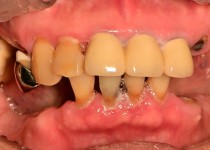

만 56세 상 하악 임플란트 증례